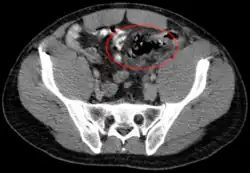

Perforation des Sigmas im Rahmen einer Divertikulitis in der Computertomographie.

Die Diagnostik basiert auf der körperlichen Untersuchung und der Ultraschalldiagnostik. Bei Verdacht auf eine Darmperforation kann oftmals freie Luft in der Röntgenübersicht oder in der Computertomographie (deutlich sensitiver) nachgewiesen werden. Die Computertomographie kann darüber hinaus häufig die Ursache (z. B. Divertikulitis, Tumor des Dickdarms) identifizieren oder Komplikationen (z. B. Abszess, Fistel) aufdecken.